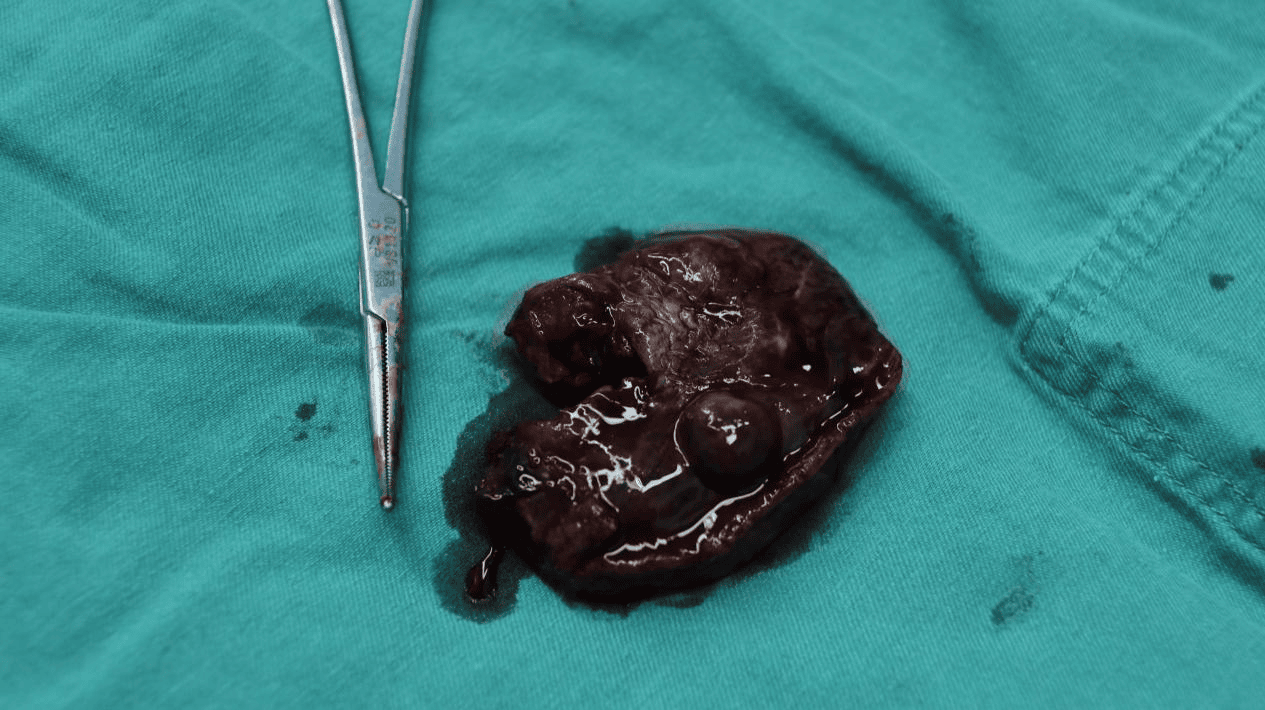

经过患者和家属同意,完善术前准备后,在曹葆强院长的指导下,普外三科团队在麻醉科及手术室的共同配合下,成功开展首例腹腔镜下左肝叶切除术,在不损伤右侧肝叶的情况下,切除直径近7cm大血管瘤。术中可见肝血管瘤与左侧膈肌黏连,腔镜下完整剥离瘤体,手术顺利,出血少,术后病人恢复快,第二天即下床自主活动。